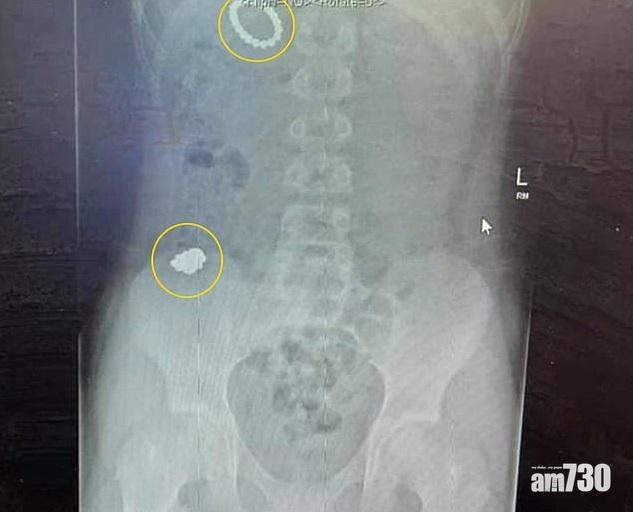

磁珠留在莫里森體內。(互聯網)

青少年有科學精神是好事,但必須理性行事。英國曼徹斯特12歲男童莫里森(Rhiley Morrison)從小沉迷科學,經常自行做實驗,但近日為測試人體內能否產生磁力,竟吞下54粒磁珠,看看磁珠會否吸住胃部,經消化後排出,磁珠又會變成甚麽模樣,但最終無法排出,幾乎喪命。

報道指,莫里森患自閉症和專注力失調及/或者過度活躍症(ADHD),估計他於1月1日吞下第一批磁珠,至4日再吞另一批,經過4天仍無法排出,便告訴媽媽自己吞下磁珠。媽媽大吃一驚,立即送他到醫院,結果莫里森須接須接受6小時手術,將胃部和腸臟內的磁珠取出,還吃盡苦頭。